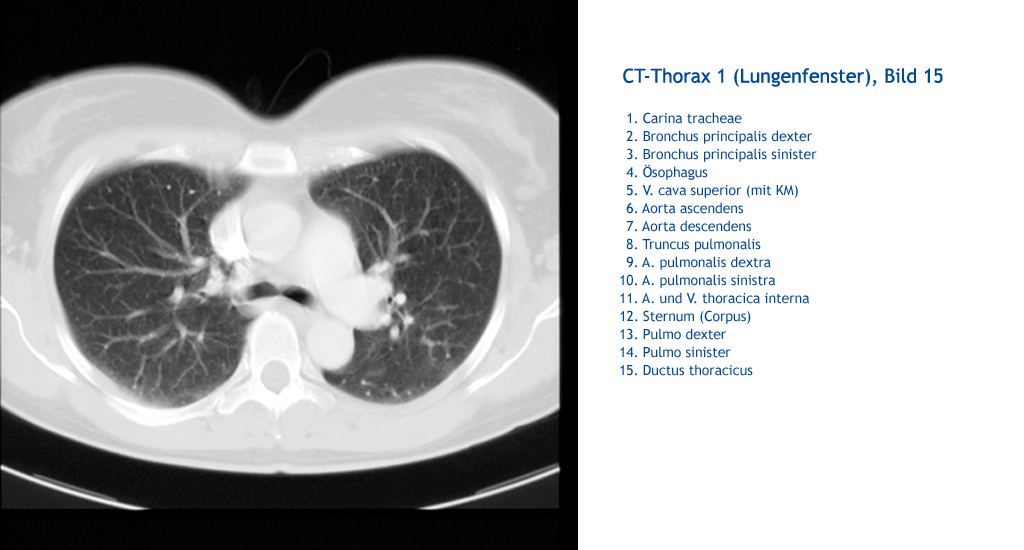

Ductus thoracicus Pulmo sinister Pulmo dexter Sternum (Corpus) A. und V. thoracica interna A. pulmonalis sinistra A. pulmonalis dextra Truncus pulmonalis Aorta descendens Aorta ascendens V. cava superior (mit KM) Ösophagus Bronchus principalis sinister Bronchus principalis dexter Carina tracheae